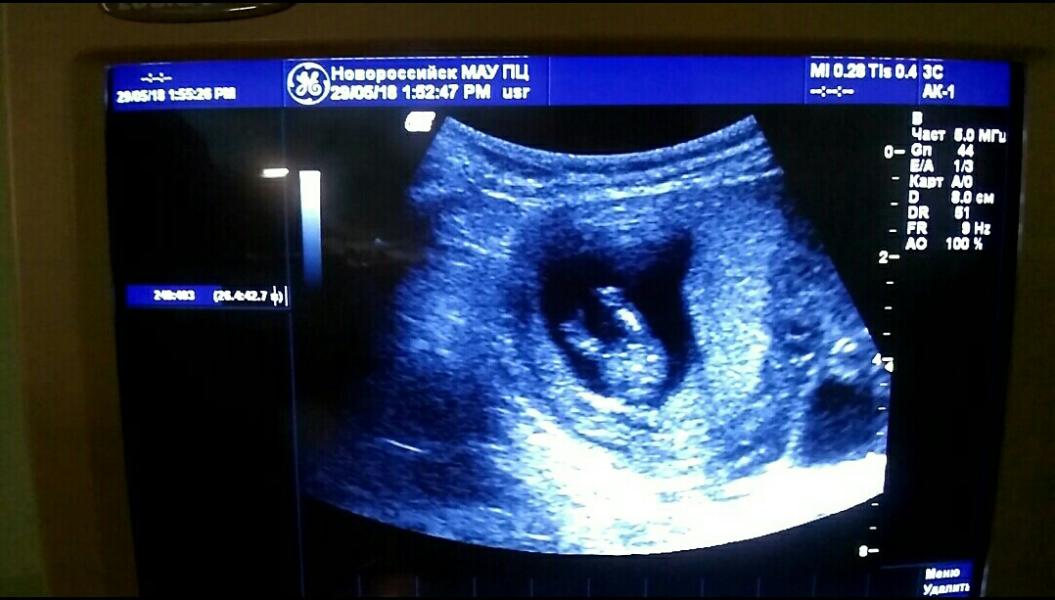

Наши первые маленькие шевелюшки 27.06.2018 😍 Мама покушала винограда 😂 А это фото УЗИ я называю: "стейк сёмги" 😂 Наша сладкая попка 😍

@smileyjul 😊 Спасибо!) Я даже не ожидала на УЗИ такого ракурса😂 С первой беременностью я и не знаю, когда у меня начались шевелюшки, глубоко не углублялась в знания беременности))) А сейчас всё так интересно для меня, будто сама первый раз забеременела 😂 Недельки через 2-3 и вы почувствуете 🙏 Говорят, сладенькое малыша расшевеливает) Я ела шоколадки, ничего не было) Сегодня вот виноградика поела) А некоторые только недель в 20 ощущают)

@iriska-2018 😂 Предположили, что дама будет 💃 Ну на следующем УЗИ точно узнаем😉

@ritakohan90 наверное, сынуля будет. Вон как лежит вальяжно 😋🤗